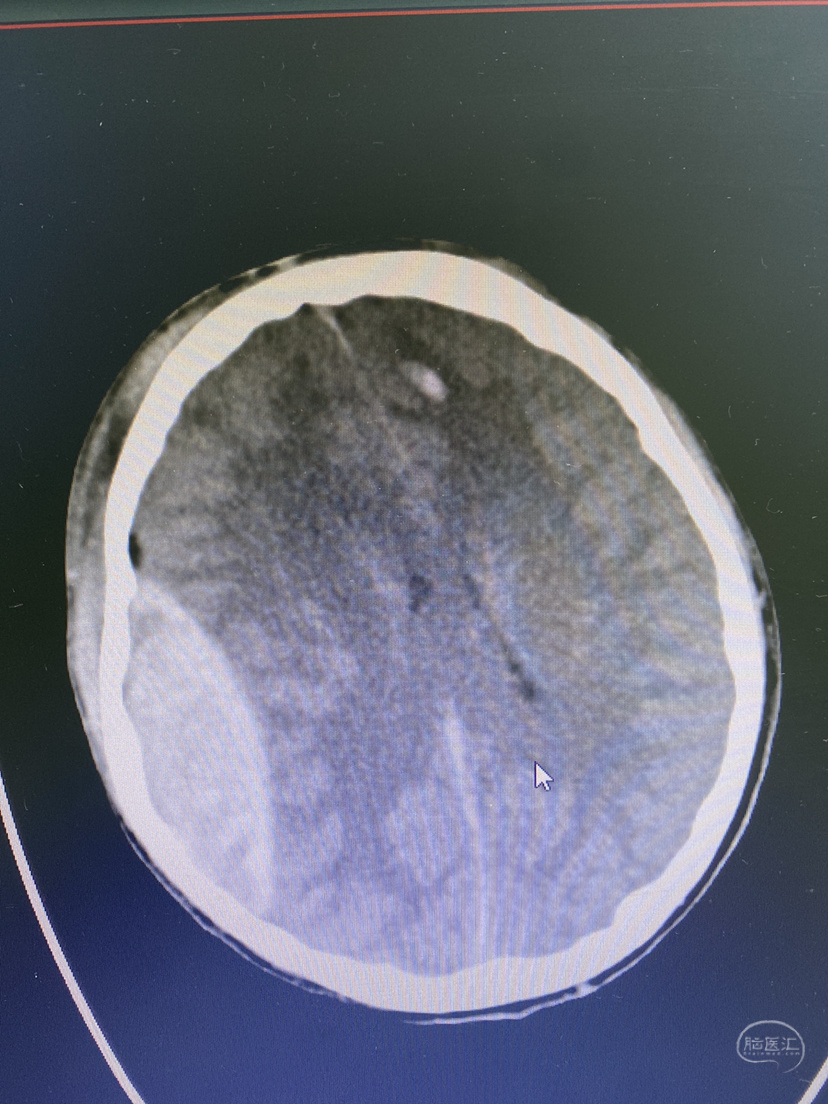

上诉处理后5天复查,积液明显减少!治疗有效!